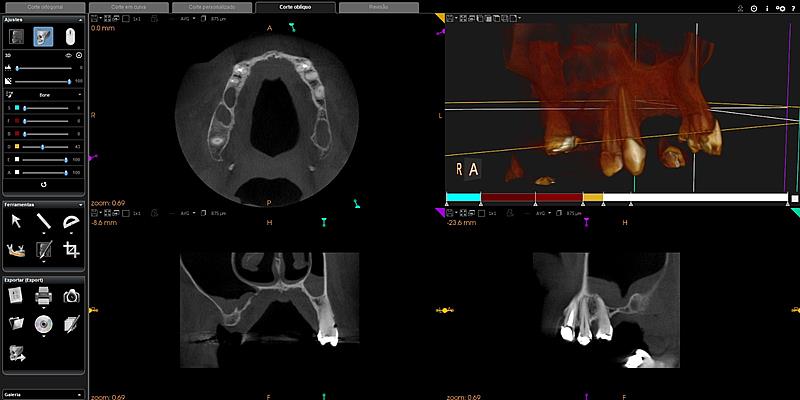

Procedimentos estéticos, cirurgias guiadas e reabilitações orais complexas têm sido realizados com maior precisão por meio de softwares que permitem simulações detalhadas e personalizadas. Um dos profissionais que acompanha de perto esse avanço é o dentista Renês Parizotto, especialista em implantodontia e mestre em prótese dentária, que atua com ferramentas digitais em sua prática clínica.

Entre os recursos utilizados está o escaneamento intraoral, que substitui as tradicionais moldagens com massa. A tecnologia permite captar imagens tridimensionais da boca do paciente com alto grau de fidelidade. Essas imagens alimentam programas que fazem desde o planejamento de cirurgias até a simulação de sorrisos, facilitando a comunicação entre o profissional e o paciente.

A impressão 3D também tem ganhado espaço nos consultórios, contribuindo para a produção de guias cirúrgicos e modelos de estudo de forma mais rápida e precisa. De acordo com Parizotto, a integração entre essas tecnologias melhora o tempo de atendimento e aumenta a previsibilidade dos procedimentos.

Mais recentemente, a inteligência artificial começou a ser aplicada em processos como análise facial automatizada, ajuste digital da mordida e simulações estéticas. Esses recursos oferecem ao dentista mais dados para decisões clínicas e permitem que o paciente visualize o possível resultado antes do início do tratamento.